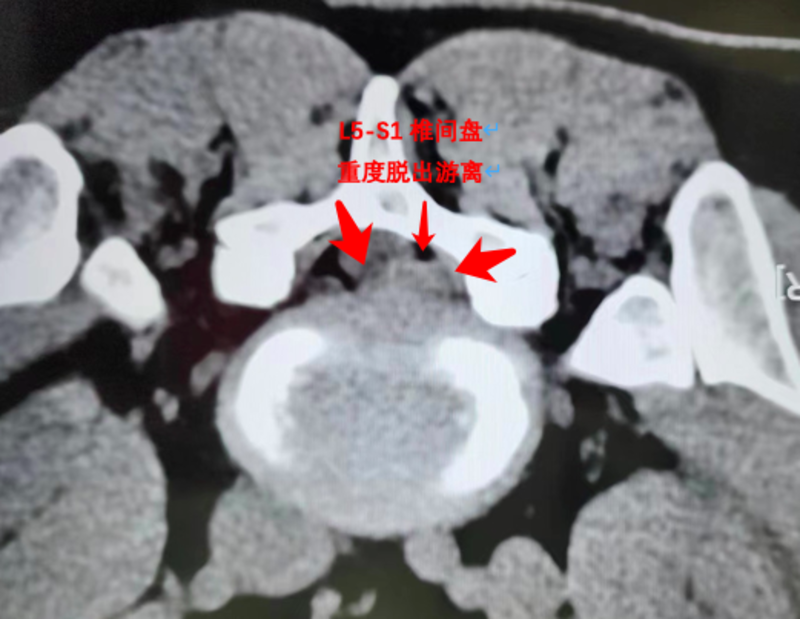

2, 2023.12.23腰椎CT;L5.S1右后脱出游离。L3.4,L4.5椎间盘退变,膨出(见图1)

2023.12.23腰椎CT;L5.S1右后重度脱出游离。

二周后再次住院二天,做了一次PRP后出院(见图2)

根据该患者严重的病情和巨大椎间盘脱出游离,如果仅仅采取椎管内消炎治疗(童氏精准无创介入治疗,)保守估计康复需要3个月(见图2)通过CT引导把PRP(富血小板血浆)直接注射到无血供组织的椎间盘内,给退变椎间盘撕裂口提供生长因子,创造修复条件,让退变椎间盘纤维环内中外三层组织结构均可以得到修复,这样不仅大大缩短了撕裂口修复的时间,同时也增强了椎间盘纤维环的坚固度。

穿刺针插入椎间盘内,注射生理盐水+造影剂,然后注射PRP(自体富血小板血浆)